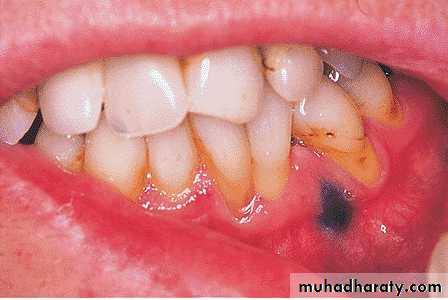

Pigmentation of the oral mucosa can occur as a result of environmental or occupationas exposure to heavy metal salts, such as mercury,Following absorption of the metals, they are deposited as metallic sulfides as a grey (or blue/black) line along the marginal gingivae.

Amalgam tattoos

Amalgam tattoos are a result of fragments of the material being embedded in the oral mucosaAmalgam tattoos may be radio-opaque

They usually occur on the floor of the mouth or alveolar mucosa, near to existing or previous amalgam restorations